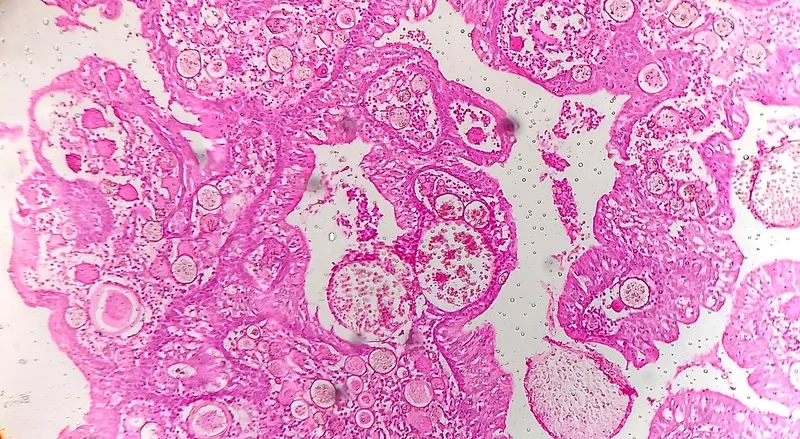

Microscopic view of Rhinosporidium seeberi